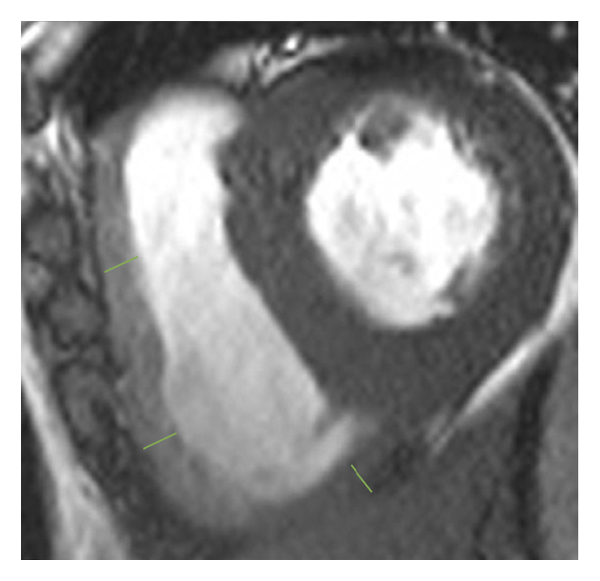

2.3. 이미징 분석모든 이미지 분석은 시중에서 판매되는 소프트웨어(cvi42, Circle Cardiovasic Imaging, Inc. Calgary, Canada)를 사용하여 수행되었습니다. 심장 기능을 측정하기 위해 심장내막 및 심외막 추적을 확장기 말기 및 수축기 말기의 직렬 단축 슬라이스에서 수동으로 수행했습니다. LV/RV 확장기말 용량(EDV), 수축기말 용량(ESV) 및 LV/RV 박출률을 포함한 전체 LV/RV 수축기 기능이 계산되었습니다. LV 및 RV 심근 스트레인 분석은 장축 4챔버 및 단축 슬라이스를 조직 추적 모듈에 로드하여 수행되었습니다(그림 1 (a) 및 1 (b)). RVT는 중실의 3회 측정하였고, 평균 두께를 계산하였다(도 1 (c) 및 1 (d)). GRPS(글로벌 라디칼 피크 변형), GLPS(글로벌 세로 피크 변형) 및 GCPS(글로벌 원주 피크 얼룩)를 포함하여 전역 특징 추적 매개변수가 자동으로 획득되었습니다. 최고 수축기 변형률(PSSR, 이완기부터 다음 수축기까지의 모든 단계에 대한 절대값의 최대 변형률)과 최고 확장기 변형률(PDSR, 수축기부터 다음 수축기까지 모든 단계에 대한 절대값의 최대 변형률)은 다음과 같습니다. 또한 분석했다. 양수 기호와 음수 기호는 서로 다른 동작 방향을 나타냅니다. 앞서 기술한 바와 같이[ 16 ], 정상적인 RVT 값은 7mm 이하로 정의되었다. 기준에 따라 CA 및 HCM 환자를 RV 비대(RVT >7 mm) 또는 RV 비대(RVT ≥7 mm) 환자에 따라 하위 그룹으로 나누었습니다.

(디)